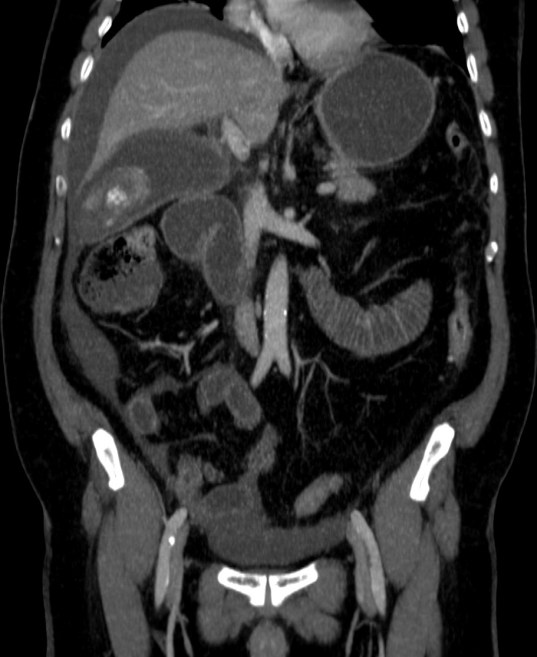

Se realizó posteriormente TC abdominal por mala evolución del paciente:

– La TC se reserva para pacientes con dudas diagnósticas o con discrepancia clínico ecográfica. Se obervarán los mismos hallazgos que en la ecografía, además del aumento de densidad de la pared de la vesícula, del parénquima hepático o especialmente la presencia de otras complicaciones.

- Colecistitis xantunogranulomatosa: nódulos o bandas intramurales. Se producen por la oclusión de los senos de Rokitansky Aschoff de la pared, los cuales se rompen, luego la bilis coloniza la pared y finalmente produce una reacción inflamatoria a la que puede sobreañadirse una infección. Es un factor de riesgo para el carcinoma.

- Eco y TC: Litiasis + engrosamiento mural focal o difuso. Puede haber cambios inflamatorios pericolecísiticos. Los nódulos hipocogénicos o bandas pueden sugerir el diagnóstico específico de c. xantunogranulomatosa.